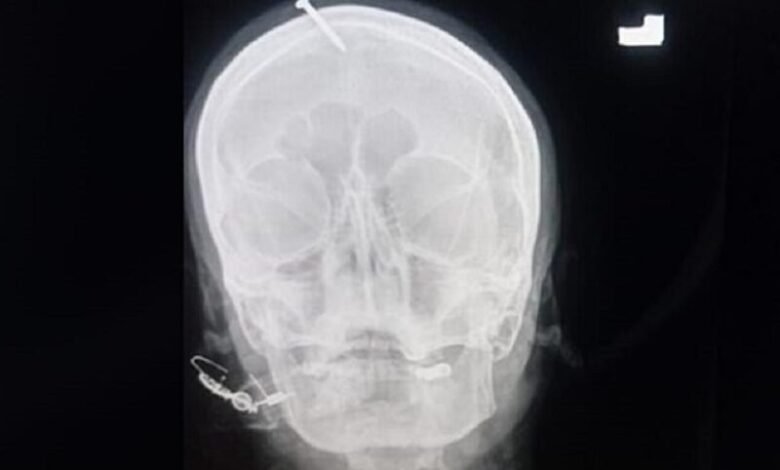

ووصلت المرأة الى احد المستشفيات في مدينة بيشاوار الباكستانية ومسمار بقياس 4 سنتيمترات مغروس في جبينها بعدما قال لها “المعالج الروحي” ان القيام بذلك سيضمن ان يكون المولود القادم ذكرا.

ويفيد أحد الاطباء بأن المرأة الحامل قد جاءت الى المستشفى بعد محاولتها نزع المسمار بنفسها. وقال انها كانت بكامل وعيها لكنها كانت موجوعة جدا. وتظهر صورة شعاعية انتشرت على الاعلام المسمار مغروسا في جبين المرأة. وأضاف الطبيب ان الرجل قد استعمل مطرقة او آلة حادة أخرى لإغراس المسمار. وقامت شرطة المدينة بالتحقيق مع المرأة ليأخذوا تفاصيل الحادثة لاتخاذ اجراءات قانونية بحق المتورطين.